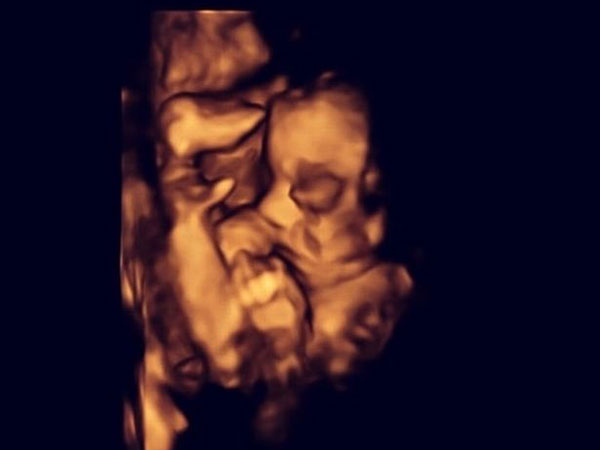

குழந்தை மறுபடி கருவில் சேர்ப்பு

தாயின் கர்ப்ப காலம் முடிய எதுவாக, அறுவை சிகிச்சைக்கு பின்னர், குழந்தை மீண்டும் தாயின் கருப்பைக்குள் வைக்கப்படும். இந்த அறுவை சிகிச்சை வெற்றி அடைந்ததை முன்னிட்டு, மருத்துவர்கள், இந்த வகை அறுவை சிகிச்சையை பரிந்துரைக்கின்றனர். பொதுவாக இது போன்ற பிறப்புக் குறைபாடுகள் கண்டறியப்படும்போது , 80% பேருக்கு கருக்கலைப்பு பரிந்துரைக்கப்படுகிறது. இதற்கு மாற்றாக, மேலே கூறிய சிகிச்சையை மேற்கொள்வதால் குழந்தைக்கு பாதிப்பு ஏற்படாது என்று மருத்துவர்கள் கூறுகின்றனர். இந்த பதிவு பற்றி உங்கள் கருத்துகளை எங்களுடன் பகிர்ந்து கொள்ளுங்கள்.